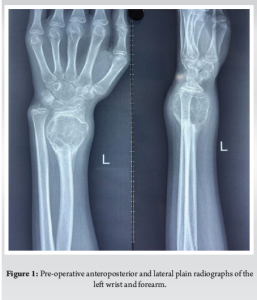

A 12-year-old, right-hand-dominant female was brought to us by her parents with complaints of pain in the left wrist for the past 4 months, swelling since 3 months, without any history of fever, effusion, weight loss, or any similar complaints in family members. On examination, there was a swelling of (5 × 4 cm) in size, non-fluctuant, non-pulsatile, non-compressible, without any local rise of temperature. Hand function and grip strength were decreased on the left side as compared with the right side and there was no neurovascular deficit. Radiographs obtained showed a metaphyseal, osteolytic lesion with cortical breach and no periosteal reaction, which seemed to point toward an osteoclastoma of the distal radius; the epiphysis seemed to have been fortunately spared (Fig. 1 and 2). This was followed up with a biopsy, which confirmed our clinical and radiological findings. The child was diagnosed with a Campanacci Grade 3 GCT of the left distal radius and planned for wide local excision and ulnar translocation.